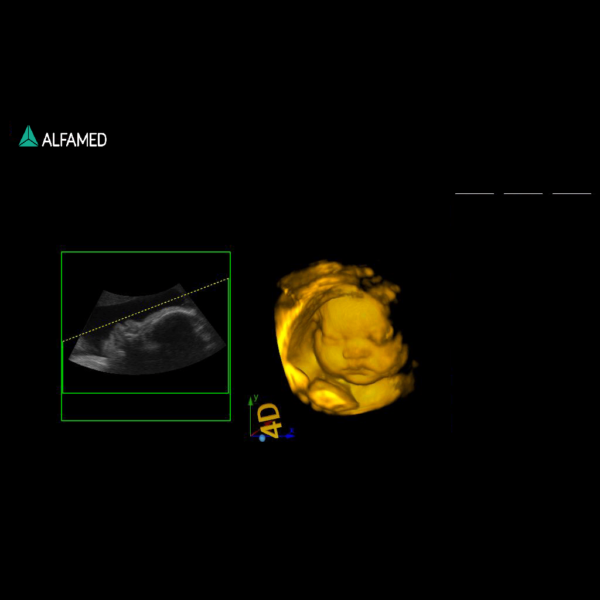

⦁ Pacote para imagem 3D e 4D em tempo real com transdutor dedicado ;

• Transdutor multifrequencial de banda larga convexo 4D com faixa de frequência ajustável de 2 a 7MHz;

• Transdutor multifrequencial de banda larga endocavitário 4D com faixa de frequência ajustável de 4 a 12MHz;